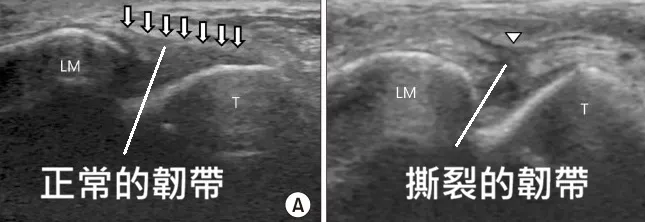

🔍 宸新精準診斷:高解析度超音波

對於舟月韌帶損傷,單靠一張普通的 X 光片往往不夠。我們採用進階的影像診斷:

高解析度超音波檢查,可清楚看到關節中間的韌帶有無受傷,關節有無分離或是有積液